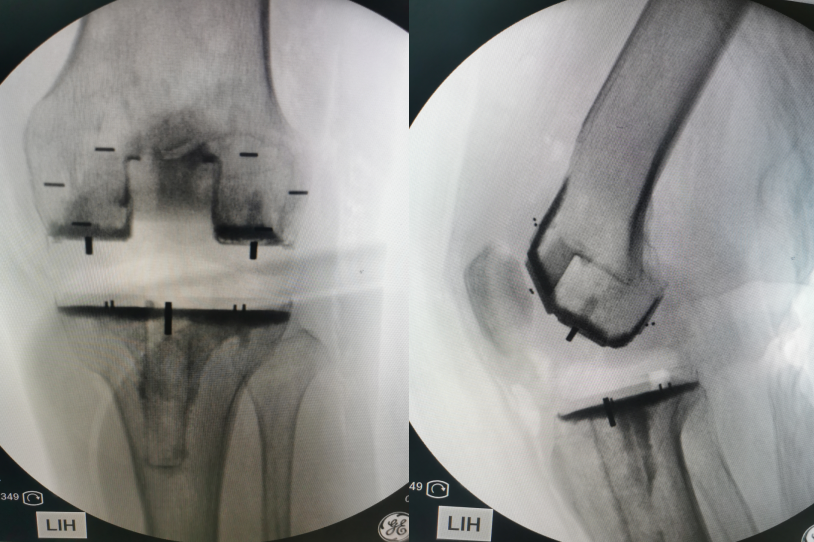

本次患者为老年女性,患有终末期骨性关节炎,下肢力线发生了严重改变。经过病史询问、体格检查及影像学检查,患者诊断明确,全膝关节置换手术是解决患者目前疾病的唯一方式。完善术前检查及充分评估后,该团队首次采用PEEK人工全膝关节并顺利完成全膝关节置换手术,不仅有效的纠正了下肢的力线,更显著的缓解了患者的痛苦。